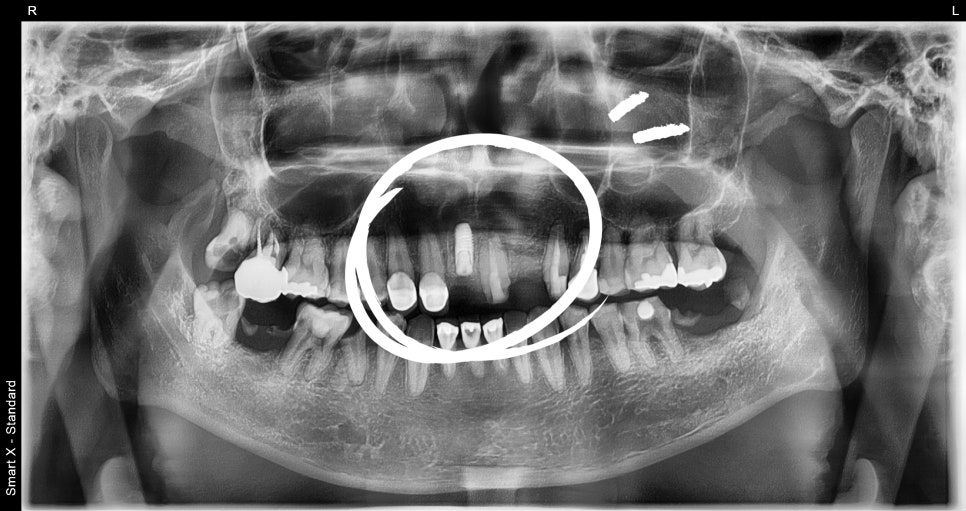

📸 Postoperative X-ray

– Complete removal of the lesion and implant placement

– Bone height secured with graft material

① Extraction of tooth #11 and cyst removal surgery

– At the same time as extraction, the 2 cm cyst lesion was completely removed.

– Allograft bone was also placed in the bone area resorbed by the cyst.

② Same-day implant placement

– After carefully checking the bone condition, surgery was performed at the depth and angle suitable for immediate placement.

– Since this was the anatomically important front tooth area, precise angle and depth control were necessary.